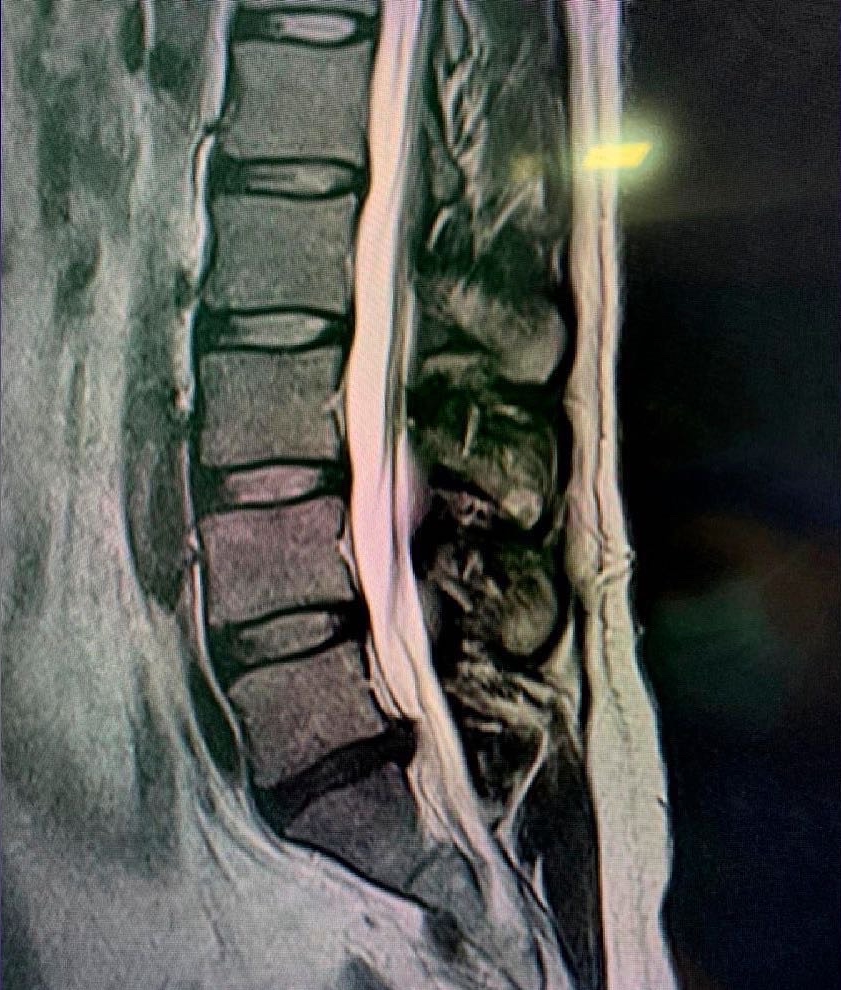

Disc disease

Disc disease is probably the disease most frequently treated by neurosurgeons and spine surgeons. Acute disc prolapse, bulging disc, herniated disc or ruptured disc are terms commonly used to describe failure of this structure. When symptoms are new, the typical sequence is first back pain in the region of the disc followed by nerve irritation pain in the arm or leg. This is called radicular pain, and some people use the term sciatica when the leg is affected.

A long-standing prolapsed disc may lead to chronic back, neck, arm, shoulder or leg pain, in any combination. All three parts of the mobile spine can be affected, but the lumbar and cervical regions are much more likely to cause symptoms. This is due to the relative mobility and loads placed on these regions.

Symptoms cause pain that usually worsens with loading and lifting and is relieved by rest or flexed positions. Arm or leg pain is very common and, when more severe, there may be limb numbness or weakness or hand dysfunction. The distribution of pain or neurological symptoms is determined by the affected nerve and depends on whether the disc is of cervical, thoracic or lumbar origin. When spinal cord compression is present, gait, balance and continence may be affected. Surgery is recommended when there is a significant neurological problem or if the pain does not respond well to simple measures. Simple discectomy, microdiscectomy, minimally invasive discectomy or anterior cervical discectomy and arthrodesis can be very effective in selected patients who do not respond to rest, analgesia and other conservative measures.

Another problem that commonly affects the disc is degenerative disc disease which can cause disabling symptoms such as pain, loss of limb strength, difficulty walking, etc. This can affect any region or area of the spine, but mainly the cervical and lumbar spine. These problems may require treatments ranging from physical therapy to complex surgeries involving disc replacement and support with screws.